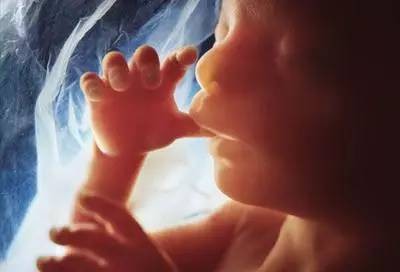

第八个月

胎宝宝身长约40cm,体重约1800g,此时的胎宝宝已经充满整个子宫,生长迅速,活动空间变小,皮下逐渐长出脂肪,大脑迅速发育,眼睛开闭自由,可以辨认和追踪光源。